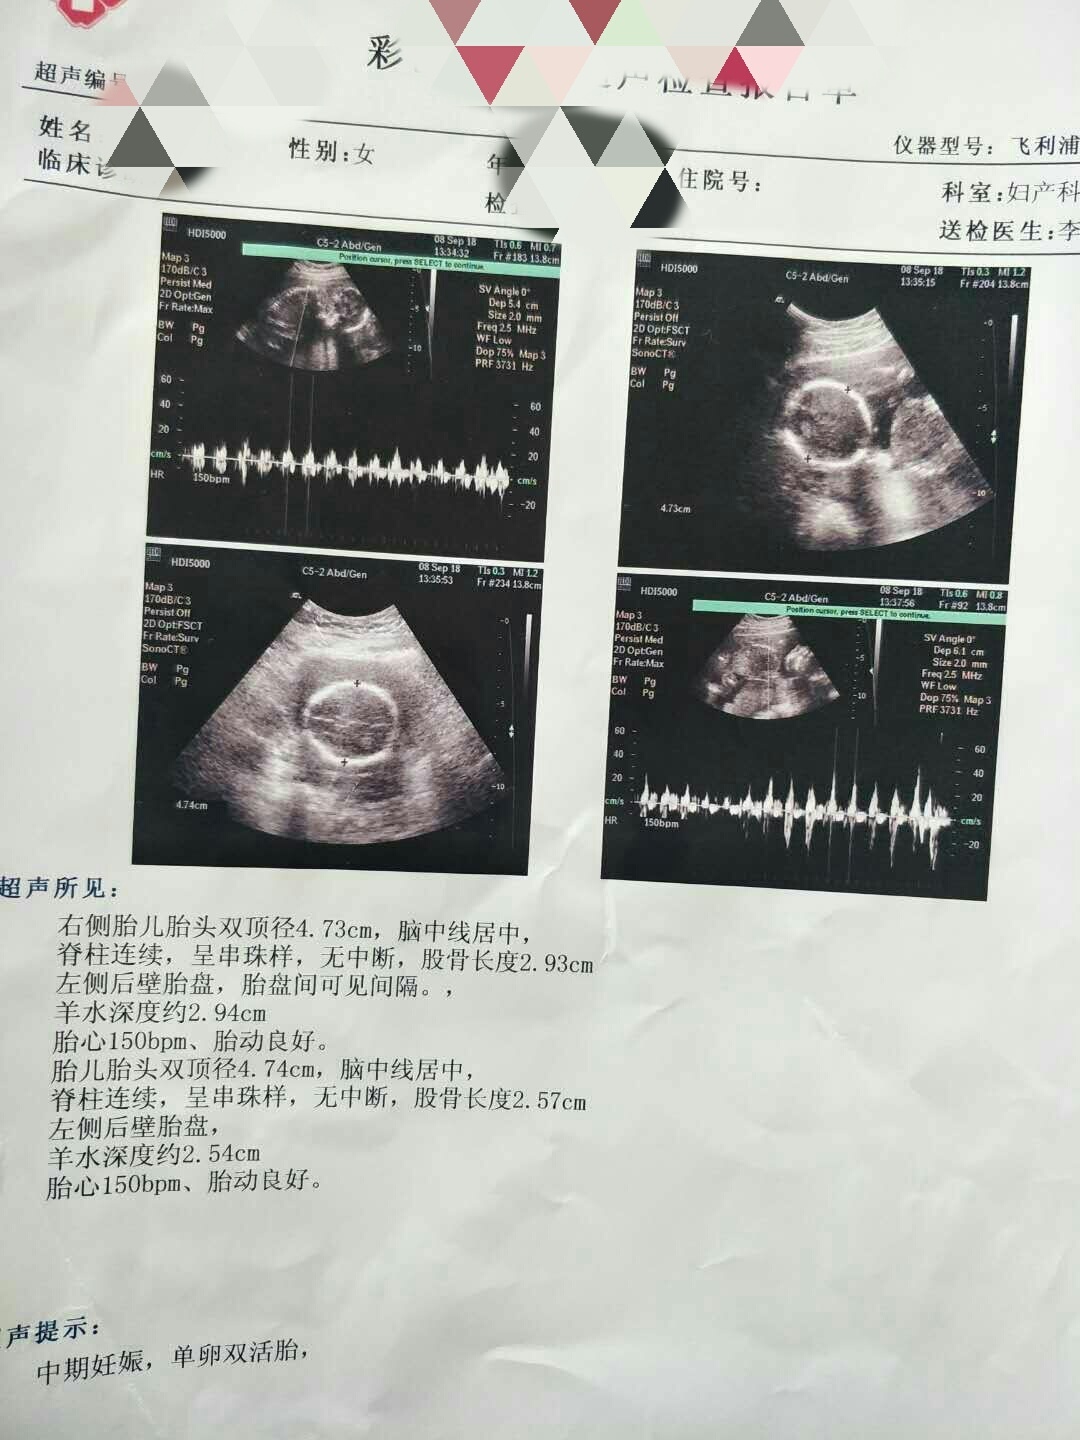

可乐双胞胎兄弟

2018-06-01

2736 人回复